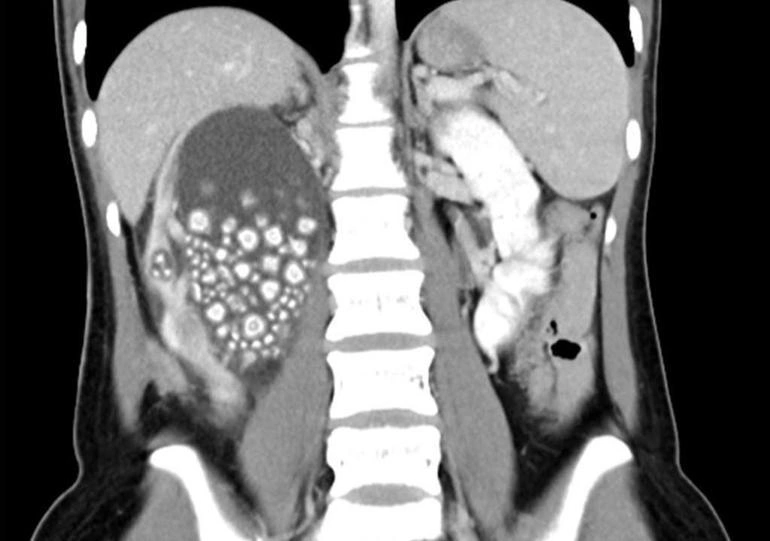

Bel ağrısından şikayətləndi: Qadının böyrəyindən 300 daş çıxarılıb